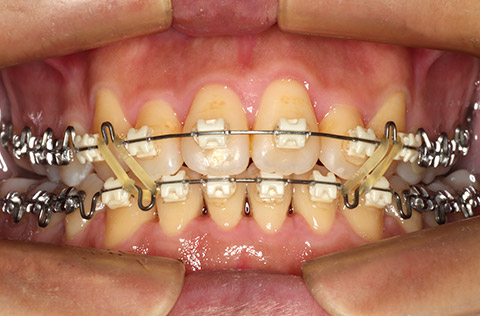

オーストリア咬合学を基に、GUMメタルワイヤーとGEAR法で、開口などの骨格性不正咬合を非抜歯で治療できたケース。